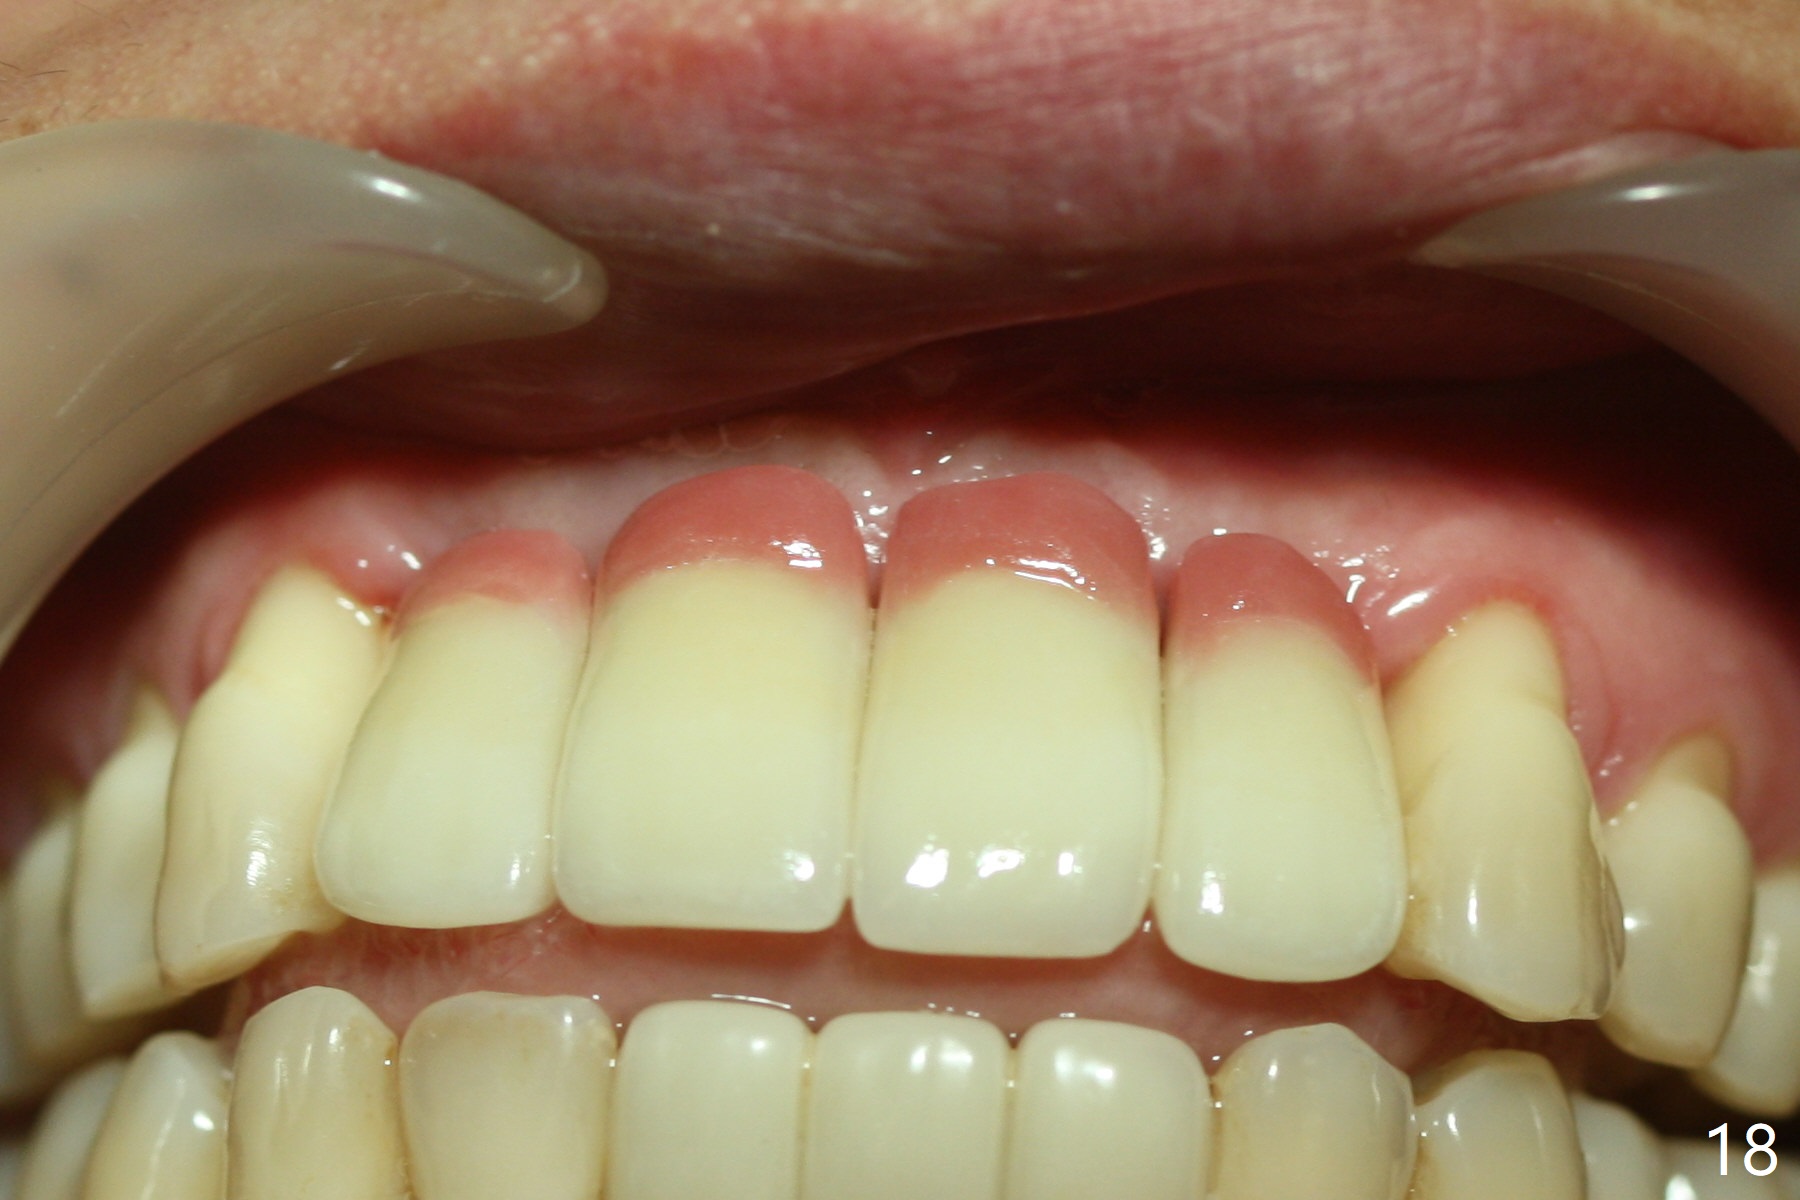

Although the ridge of the maxillary anterior ridge looks moderate in width (Fig.1), the bone is ~4 mm buccopalatally. Suction down surgical stent (Fig.2') made from the lab-fabricated provisional (Fig.2) will be used to check the position and trajectory of osteotomies. PAs taken after initial osteotomies (1.2 mm drill) show those at the central incisors tend to be mesial (close to the Incisive Canal *), while those at the lateral incisor sites distal (Fig.3,4). After adjustment, the position and trajectory of the osteotomies are acceptable (Fig.5,6). To reduce the chance of perforating the Incisive Canal (Fig.3,4 *), 2.5 mm 1-piece implants are inserted with >40 Ncm (Fig.7,8). After deep placement of the implants, Vanilla graft is placed at the crest (Fig.9,10 *). An immediate splinted provisional is fabricated from the suction down stent. The gingiva is healthy around the provisional (Fig.11) and the implants (Fig.12,13) 1 month postop. The provisional is adjusted monthly so that the interdental papillae can be elongated. No bone resorption is observed 6 months postop (Fig.14,15). Crowns are cemented 8 months postop (Fig.16-18). The keratinized gingiva appears to have formed the abutments 8 months postop immediately pre-cementation (Fig.19).